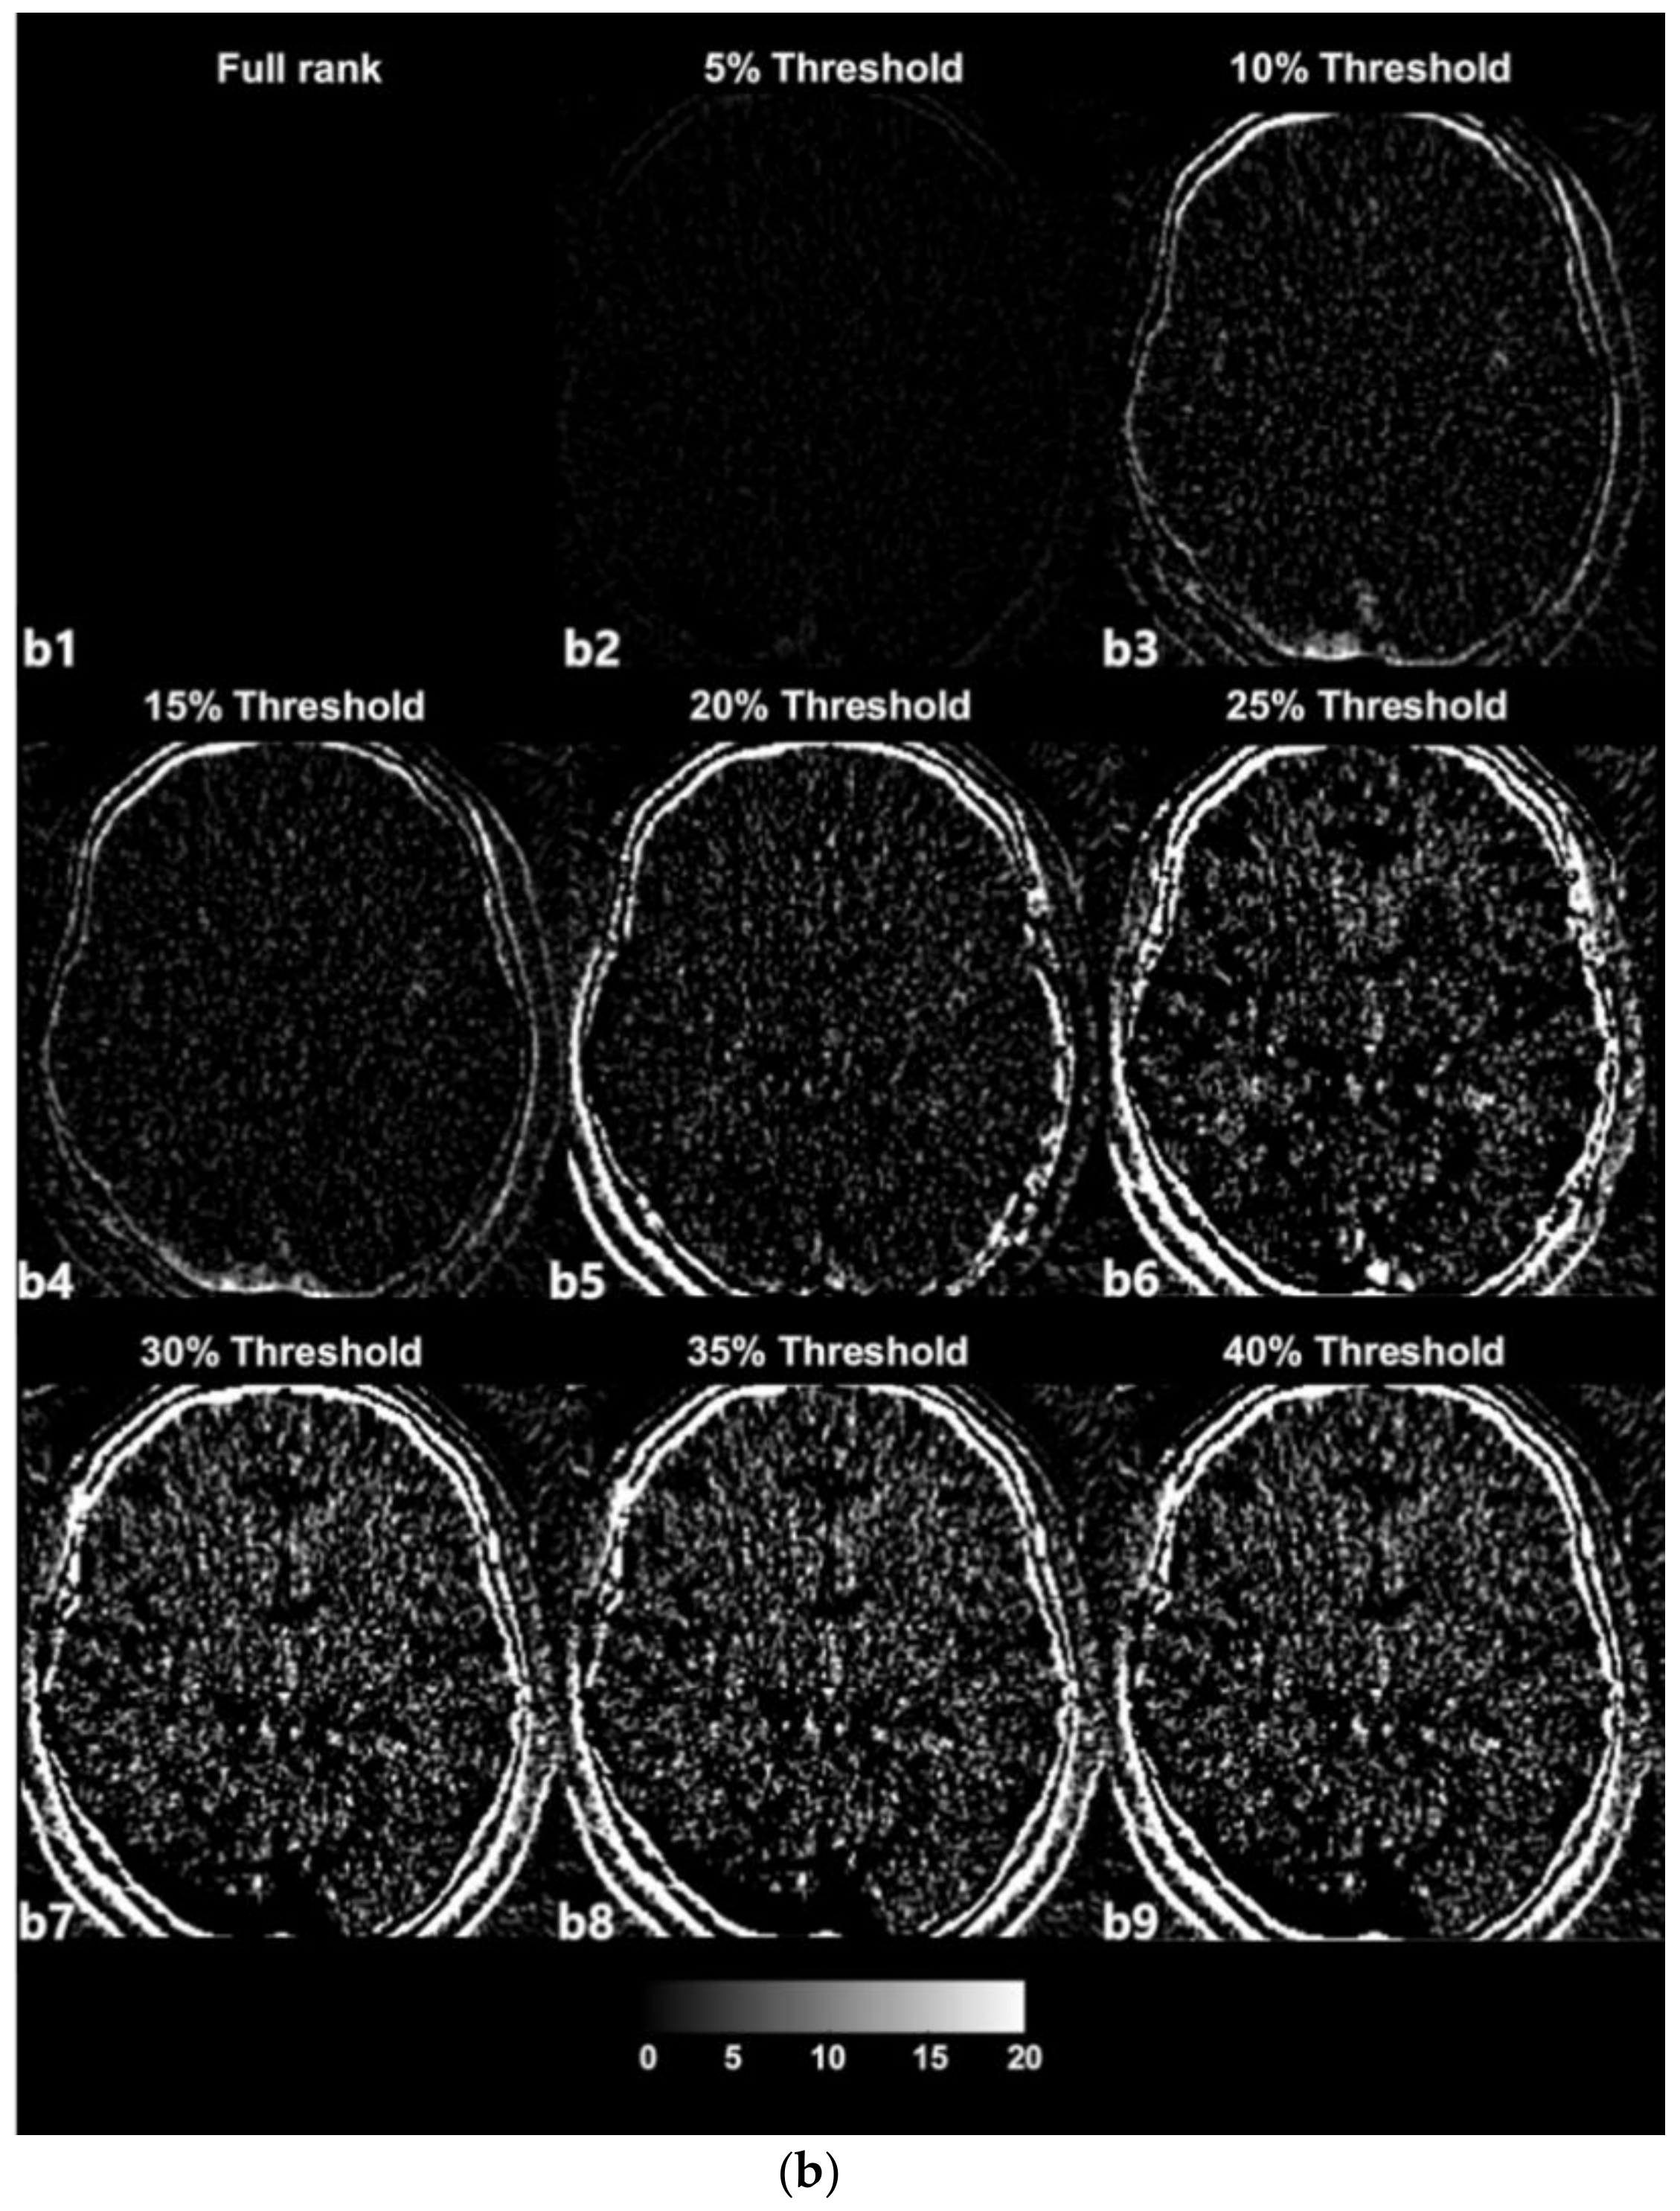

The SVD-based denoising technique was applied to 20 CTP datasets. Each dataset was reconstructed with singular values that were higher than the 5%, 10%, 15%, 20%, 25%, 30%, 35%, and 40% threshold values. Figure 3a depicts an example of denoised images corresponding to increasing thresholds. Figure 3b presents images with noise that were reconstructed with singular values lower than each threshold value and that were separated from the original full-rank image. In an example dataset, a full rank image (original noised Image) includes 27 singular value (Signal Component, SC) components. As shown in Figure 3a,b, the removal of larger amounts of Gaussian noise on an image is observed when the image is reconstructed with a smaller number of SCs (i.e., a larger number of low singular values were excluded).

Figure 3.

(a) Example of denoised images based on thresholding values; a1—original image, a2–a9—denoised images. (b) Example of separated noise components in accordance with thresholding; b1—no noise component was separated from the original image, b2–b9—noise components separated from the original image corresponding to Figure 3.

The term ‘rank’ refers to the number of singular values added to reconstruct a single image [28,29]. The number of singular values in a rank was determined in relation to the threshold value. We selected the 2nd component of the diagonal S matrix as the threshold value on an experiential basis; there is no golden rule to guide the selection of the threshold value because the boundaries of the signal and noise components are still vague and unclear (Figure 2). Thresholding was the process used to approximately classify the singular values in terms of signal components and noise components. The singular values that were lower than the set threshold percentage value (2nd component) were assumed to be singular value noise components in every condition and were subsequently reconstructed into a noise-containing image (Figure 3b). In contrast, the singular values that were higher than the set threshold percentage value (2nd component) were assumed to be singular signal components in every condition and were subsequently reconstructed into a denoised image (Figure 3a).

In the used dataset, the full-rank image (original image, a1) included 27 SCs (Figure 3a), i.e., the 1st to the 27th components, which were in decreasing order of magnitude and were not yet classified. In the case of Figure 3a from a2 to a9, with increasing threshold percentages, larger numbers of components were classified as noise components, resulting in denoised images. For example, in the case of (Figure 3a, a2), the 1st to the 20th singular values were included to reconstruct the denoised image labeled as the 5% threshold image, and the 21st to the 27th singular values that were lower than 5% of the 2nd component were separated from the full-rank image and used to reconstruct the separated noise-containing image (Figure 3b, a9). The image a9 that is labeled as 40% of the threshold image was reconstructed including only the 1st and 2nd singular values by separating the largest number of SCs (25 SCs) from the full-rank image. Nonetheless, the image still appears to exhibit sufficiently high image quality. Regarding image a9, the 1st and 2nd singular values are predominantly depicted as providing diagnostic information. However, it is difficult to confirm that the image at the 40% threshold is the best one, as it simply involves the separation of a larger number of noise-related patterns; reducing the noise on a medical image is inevitably a trade-off for acquiring diagnostic information.